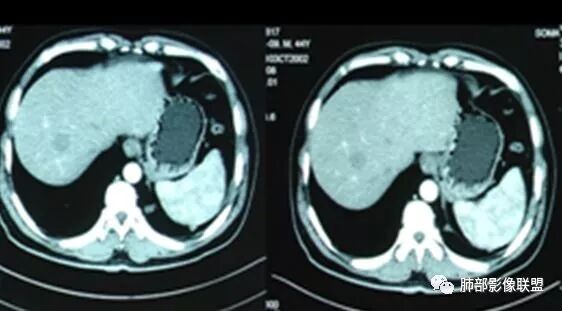

腹增强CT

南边:胸膜下,类圆形,边界清,内有坏死,典型的反晕征,支气管壁增厚不明显,支持血道来源脓毒栓子所致梗死、感染

血道来源没问题

左下叶大片类似病灶

脾大,肝内结节中央似有点状血管通过,炎性可能

2.本例应当属另一经典感染途径,肝脏感染,双肺脓毒性肺炎。大家都注意到患者的基础疾病,糖尿病。

4.本例肝脏的病灶并未出现典型肝脓肿图像特征,病灶密度及中央血管样结构显然不符合一般的囊肿。应当说,它是感染灶,但并未液化形成脓腔。